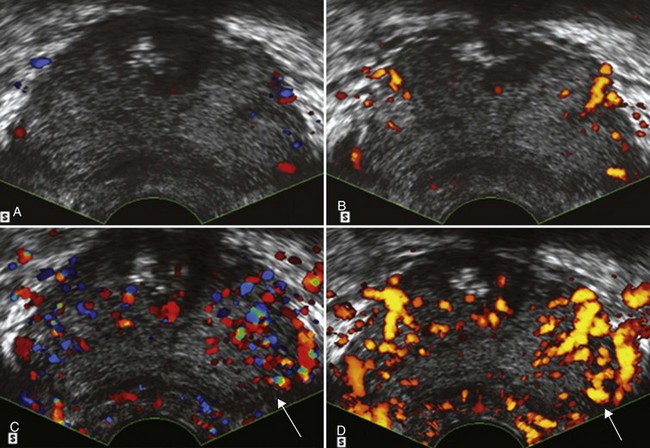

Using contrast-enhanced TRUS (CE-TRUS) for prospective prostate cancer detection, Halpern and associates (Halpern et al, 2001) demonstrated an increase in sensitivity from 38% to 65% versus baseline unenhanced imaging, without significantly altering specificity. Subsequent studies by our group and others have improved sonographic detection of malignant foci using CE-TRUS and targeted biopsy of enhancing lesions (Frauscher et al, 2001; Halpern et al, 2002a; Roy et al, 2003; Halpern et al, 2005; Heijmink and Barentsz, 2007). In a multi-institutional trial involving several European centers, CE-TRUS has been recommended for routine care in prostate biopsy (Wink et al, 2008). Imaging using microbubble contrast agents combined with three-dimensional image reconstruction of enhanced power Doppler images also demonstrated increased diagnostic accuracy (Unal et al, 2000) (Fig. 97–7).Gray-scale harmonic imaging is a relatively newer method for imaging ultrasound contrast agents that provides better spatial and temporal resolution compared with color Doppler imaging. A variation on gray-scale harmonic imaging, flash-replenishment imaging, provides improved visualization of neovessels that are below the standard resolution of even gray-scale ultrasonography. Flash-replenishment imaging uses a combination of high-power flash pulses to destroy contrast microbubbles, followed by low- power pulses to demonstrate contrast replenishment. A composite image is constructed depicting the vascular architecture through maximum intensity capture of temporal data in consecutive low-power images, and it can be used for real-time targeted transrectal biopsy of areas of increased or abnormal vascularity. Using this technique, we have demonstrated much finer vascular detail for targeting biopsy, and targeted biopsy cores were significantly more likely to be cancerous than random systematic biopsy cores (Linden et al, 2007) (Fig. 97–8). Future developments in these and other imaging modalities that can selectively visualize prostate cancers based on the presence of angioneogenesis may ultimately allow more accurate localization of the sites of cancer.

Figure 97–7 Unenhanced color (A) transrectal ultrasonography (TRUS) and power Doppler (B) TRUS fail to detect evidence of an underlying malignancy. After infusion of a microbubble contrast agent, color (C) TRUS and power Doppler (D) TRUS demonstrate an area of increased flow in the left midgland that proved to be a Gleason 3 + 4 = 7 adenocarcinoma on targeted biopsy (arrows).